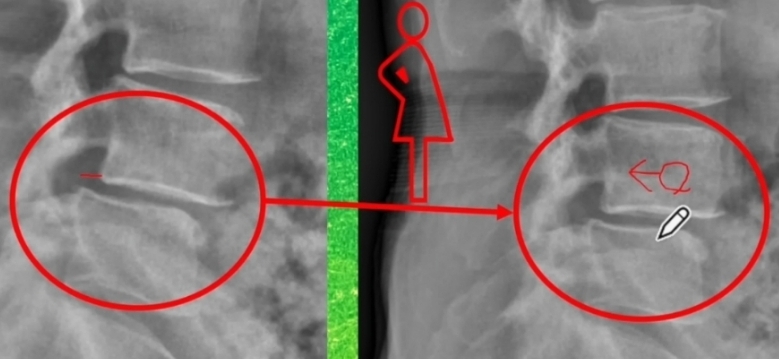

하나의 척추가 인접하는 밑의 척추에 비해 정상적인 정렬을 이루지 못하고 앞으로 빠져있는 상태.

2) 퇴행성 디스크

: 나이가 들면서 디스크 손상으로 척추의 불안정성이 높아지면서 발생